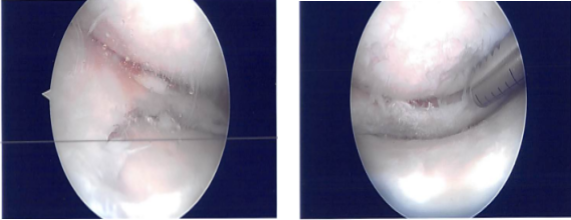

There was fraying of the inner edge of the medial meniscus. There was OA grade 1 to grade 2 damage on the femoral condyle. The meniscus was debrided to a stable margin. A chondroplasty was performed in the medial femoral condyle.

The scope was entered to the intercondylar notch and entered in the lateral femoral condyle and found fraying of the inner margin of the lateral meniscus along with the small tear. Partial meniscectomy of the inner edge was performed.

Attention was focused on the patellofemoral joint where there was osteochondral damage, grade 1 to grade 2 on the medial articular surface of the patella. It was debrided to a stable margin. There was a large osteochondral damage, grade 2 to grade 3 over the trochlea, which also debrided. Final pictures were taken.